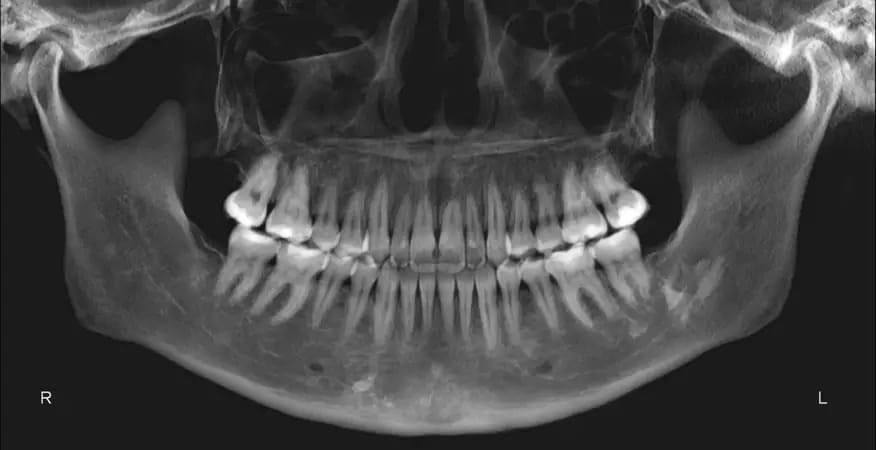

Панорамная рентгенограмма показала предварительное удаление всех третьих моляров, локальную резорбцию корней нескольких зубов, в целом хорошее состояние пародонта и атипичную морфологию мыщелков, свидетельствующую о ремоделировании височно-нижнечелюстного сустава (ВНЧС) или дегенеративных изменениях (фото 19). Цефалометрическая рентгенограмма и трассировка выявили мезобрахиально-лицевой тип скелета и тенденцию к формированию скелета II класса (фото 20).

Фото 19: Дооперационная панорамная рентгенограмма.